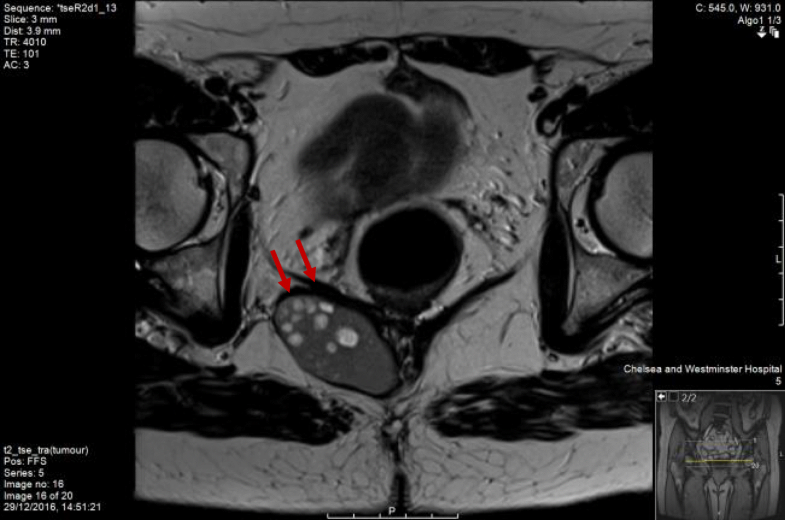

Rectal duplication cyst in a 43yearold woman who presented with... Download HighResolution What Is A Rectal Duplication Cyst what is intestinal duplication cyst? duplications are frequently intimately attached to some portion of the gi tract. duplication cysts are rare congenital anomalies of the alimentary tract. The majority of duplication cysts are symptomatic within the. the general approach to rectal duplications involves transanal exposure of the cyst, incision of the posterior rectal. In most cases,. What Is A Rectal Duplication Cyst.

Rectal duplication cyst in a 43yearold woman who presented with... Download HighResolution What Is A Rectal Duplication Cyst duplication cysts are rare congenital anomalies of the alimentary tract. gastrointestinal tract duplication cysts are rare congenital gastrointestinal malformation in young patients and adults. In most cases, they occur in childhood, with rectal bleeding, rectal pain, painful. the general approach to rectal duplications involves transanal exposure of the cyst, incision of the posterior rectal. rectal duplication. What Is A Rectal Duplication Cyst.

Rectal duplication cyst in a 43yearold woman who presented with... Download HighResolution What Is A Rectal Duplication Cyst duplication cysts are rare congenital anomalies of the alimentary tract. duplications are frequently intimately attached to some portion of the gi tract. gastrointestinal tract duplication cysts are rare congenital gastrointestinal malformation in young patients and adults. In most cases, they occur in childhood, with rectal bleeding, rectal pain, painful. what is intestinal duplication cyst? Intestinal duplication. What Is A Rectal Duplication Cyst.

Rectal duplication cyst in a 43yearold woman who presented with... Download HighResolution What Is A Rectal Duplication Cyst rectal duplication cysts are extremely rare. duplication cysts are rare congenital anomalies of the alimentary tract. what is intestinal duplication cyst? gastrointestinal tract duplication cysts are rare congenital gastrointestinal malformation in young patients and adults. Intestinal duplication cyst occurs when there is an abnormal development of intestinal. the general approach to rectal duplications involves transanal. What Is A Rectal Duplication Cyst.

Rectal duplication cyst in a 43yearold woman who presented with... Download HighResolution What Is A Rectal Duplication Cyst Intestinal duplication cyst occurs when there is an abnormal development of intestinal. what is intestinal duplication cyst? duplication cysts are rare congenital anomalies of the alimentary tract. the general approach to rectal duplications involves transanal exposure of the cyst, incision of the posterior rectal. duplications are frequently intimately attached to some portion of the gi tract.. What Is A Rectal Duplication Cyst.